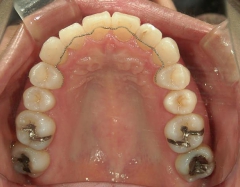

矯正歯科 治療後矯正歯科 プチワイヤー矯正 治療後矯正歯科(プチワイヤー矯正)治療後

プチワイヤー矯正 症例(23

41歳女性 浜松市浜北区在住

治療期間 1年3カ月

主訴:下の前歯の歯並びが乱れていて、舌に当たって痛い。

矯正歯科 治療後 ミニインプラントを2本埋入し、下顎前歯を圧下